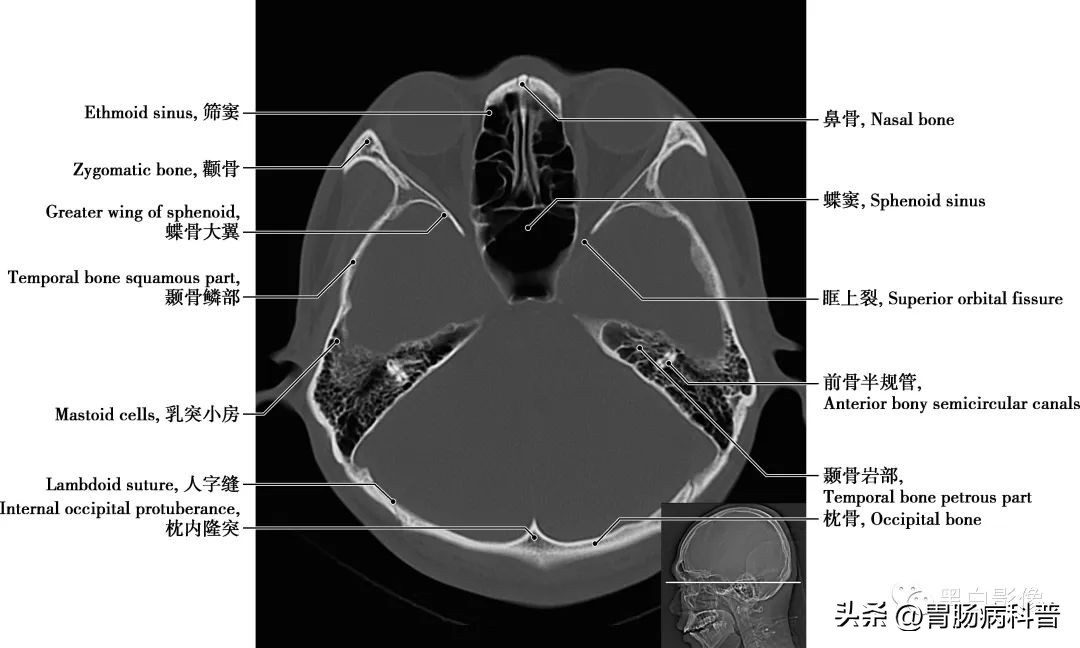

图1-2-15 经第四脑室下部轴位切面

耳蜗 为内耳的一个解剖结构,和前庭迷路一起组成内耳骨迷路,是传导并感受声波的结构,位于骨前庭的前内侧,形似蜗牛壳,耳蜗的中轴称蜗轴,呈圆锥形,由一条骨蜗螺旋管环绕蜗轴旋转二又四分之三圈而成

图1-2-16 经第四脑室侧孔轴位切面

颈内动脉 分为颅外段又称颈段,自颈总动脉分叉处至颅底。颅内段分为七段:C 1 颈段、C 2 岩段、C 3 破裂(孔)段、C 4 海绵窦段、C 5 床段、C 6 眼段和C 7 交通段。分支分布于视器和脑